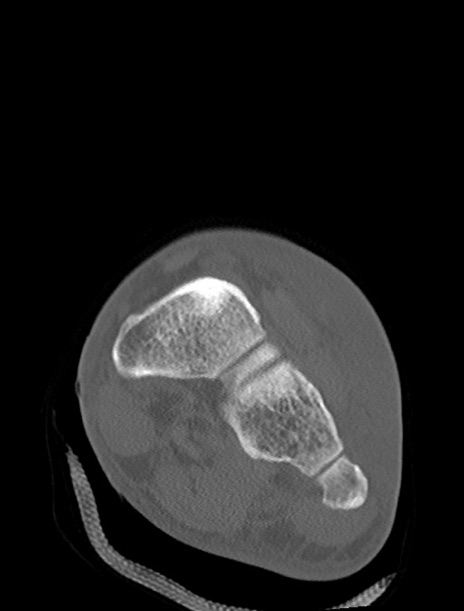

症例37 左足関節CT(冠状断像)

左足関節CT

横断像